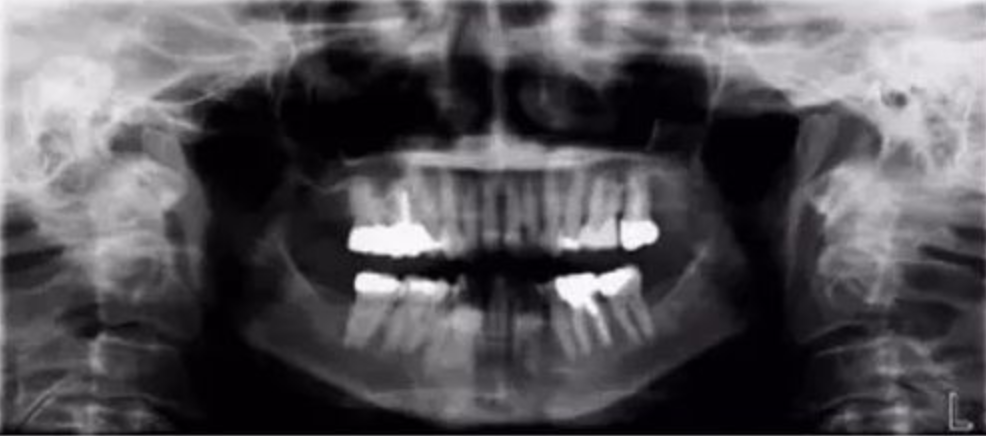

七、前牙下颌区辐射穿透度不够

【失误原因】

铅衣在患者背后位置过高。

【解决方法】

拉高患者胸前铅衣位置,拉低患者背后铅衣位置。